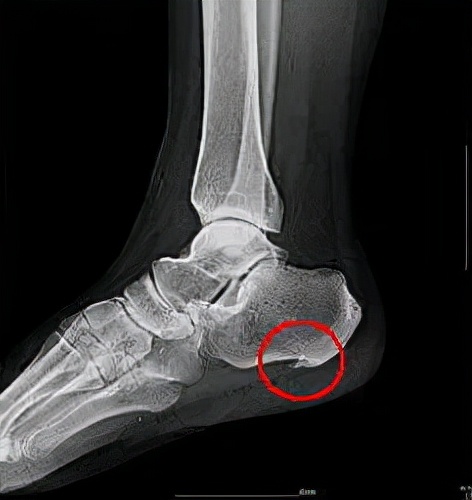

- X线

跟骨侧位或轴位,可观察跟骨局部有无骨刺形成,也可与其它疾病相鉴别。